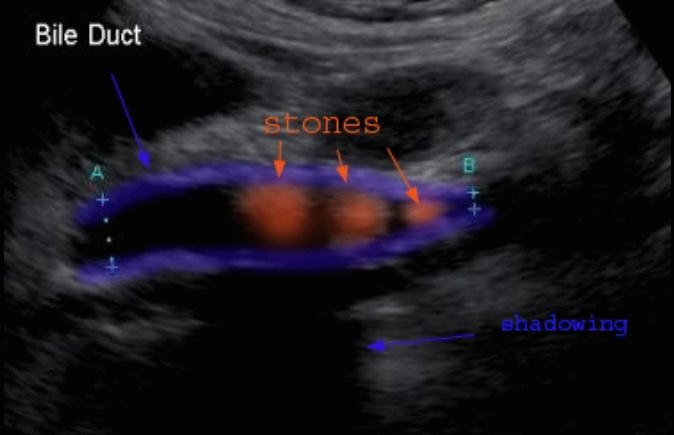

- 담석이 관찰되지 않고 간외, 간내담관의 확장소견을 시사하는 엽총징후(shotgun sign)이나 평행관 징후(parallel channel sign)가 관찰되기도 한다.

- 엽총징후(shotgun sign): 간외 담관이 확장되어 간외 담관과 문맥이 이웃해 관찰된다.

- 평행관 징후(parallel channel sign): 간내 담관이 확장되어 인접하고 있는 문맥과 나란히 2개의 관상구조로 나타난다.